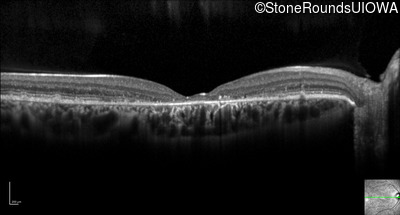

Optical Coherence Tomography - Left - 20/60

Exemplar / OCT Stack